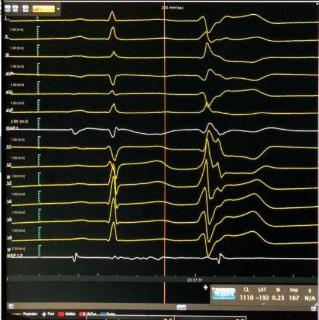

30 秒

<p>根据心电图判断室早起源位置&#xff0c;选出最可能答案。</p>

根据心电图判断室早起源位置,选出最可能答案。

LCC

RCC

LCC&RCC 之间

AC